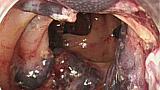

Процедуры высокого риска

1.Полипэктомия

2.Эрхпг с сфинктеротомией

3.Ампулэктомия

4.EMR/ESD

5.Дилятация стриктур

6.Лигирование ВРВ

7.Чрезкожная эндоскопическая гастростомия

8. ЭУС с тонкоигольной биопсией

9.Стентирование пищевода, тонкой и толстой кишки.